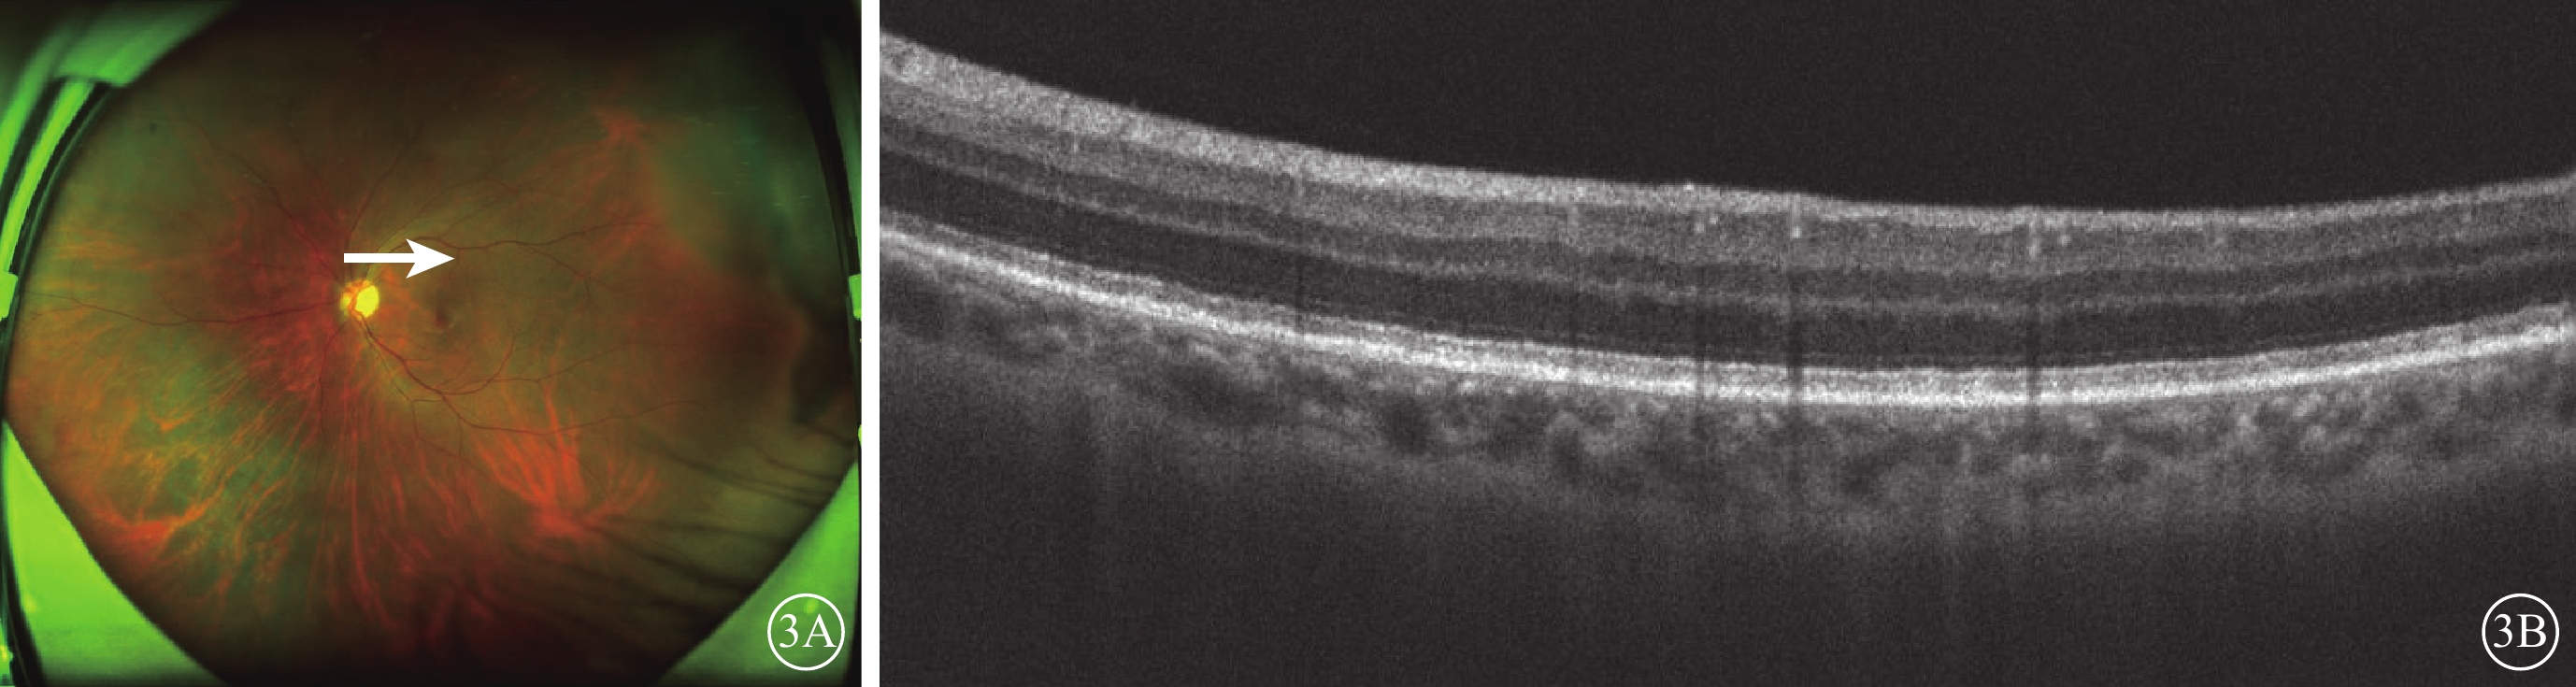

2020年10月11日,患者因左眼視力下降4 d于我院復查。右眼BCVA無光感,左眼BCVA 0.6。右眼、左眼眼壓分別為14、12 mm Hg。雙眼玻璃體混濁(+)。眼底檢查,右眼視網膜可見陳舊性病灶(圖2A);左眼鼻下象限視網膜見片狀灰白色病灶,夾雜少量出血灶,顳上及后極部視網膜可見視網膜下呈簇狀分布的點狀白色病灶(圖2B)。眼底自身熒光檢查,左眼后極部視網膜呈“豹斑樣”熒光改變(圖2C);右眼全視網膜散在大量點片狀弱熒光。FFA檢查,左眼鼻下方視網膜血管壁見熒光素滲漏,后極部視網膜呈“豹斑樣”改變(圖2D,2E)。進一步OCT掃描左眼后極部白色點狀病灶處,可見RPE上下多個結節樣強反射病灶(圖2F)。左眼房水檢測,IL-10值顯著升高至248.9 pg/ml(參考值范圍0.0~5.0 pg/ml)、IL-10/IL-6比值升高至3.62,CMV等病毒的核酸拷貝數為0,IgG正常。我院血液科會診行骨髓穿刺、頭顱、腹部CT等檢查后,未發現其他臟器淋巴瘤復發表現。經多科會診,結合患者病史,診斷:原發于中樞神經系統的彌漫性大B細胞淋巴瘤左眼眼內復發,即眼內淋巴瘤(IOL)。血液科認為無需全身化療。遂給予左眼玻璃體腔注射甲氨蝶呤治療,共9次。2021年2月復查,患者全身情況穩定。左眼視力1.0;左眼鼻下及顳上視網膜病灶均明顯消退(圖3A);OCT檢查,左眼后極部視網膜強反射病灶基本消退(圖3B)。2021年9月隨訪,患者病情未復發。